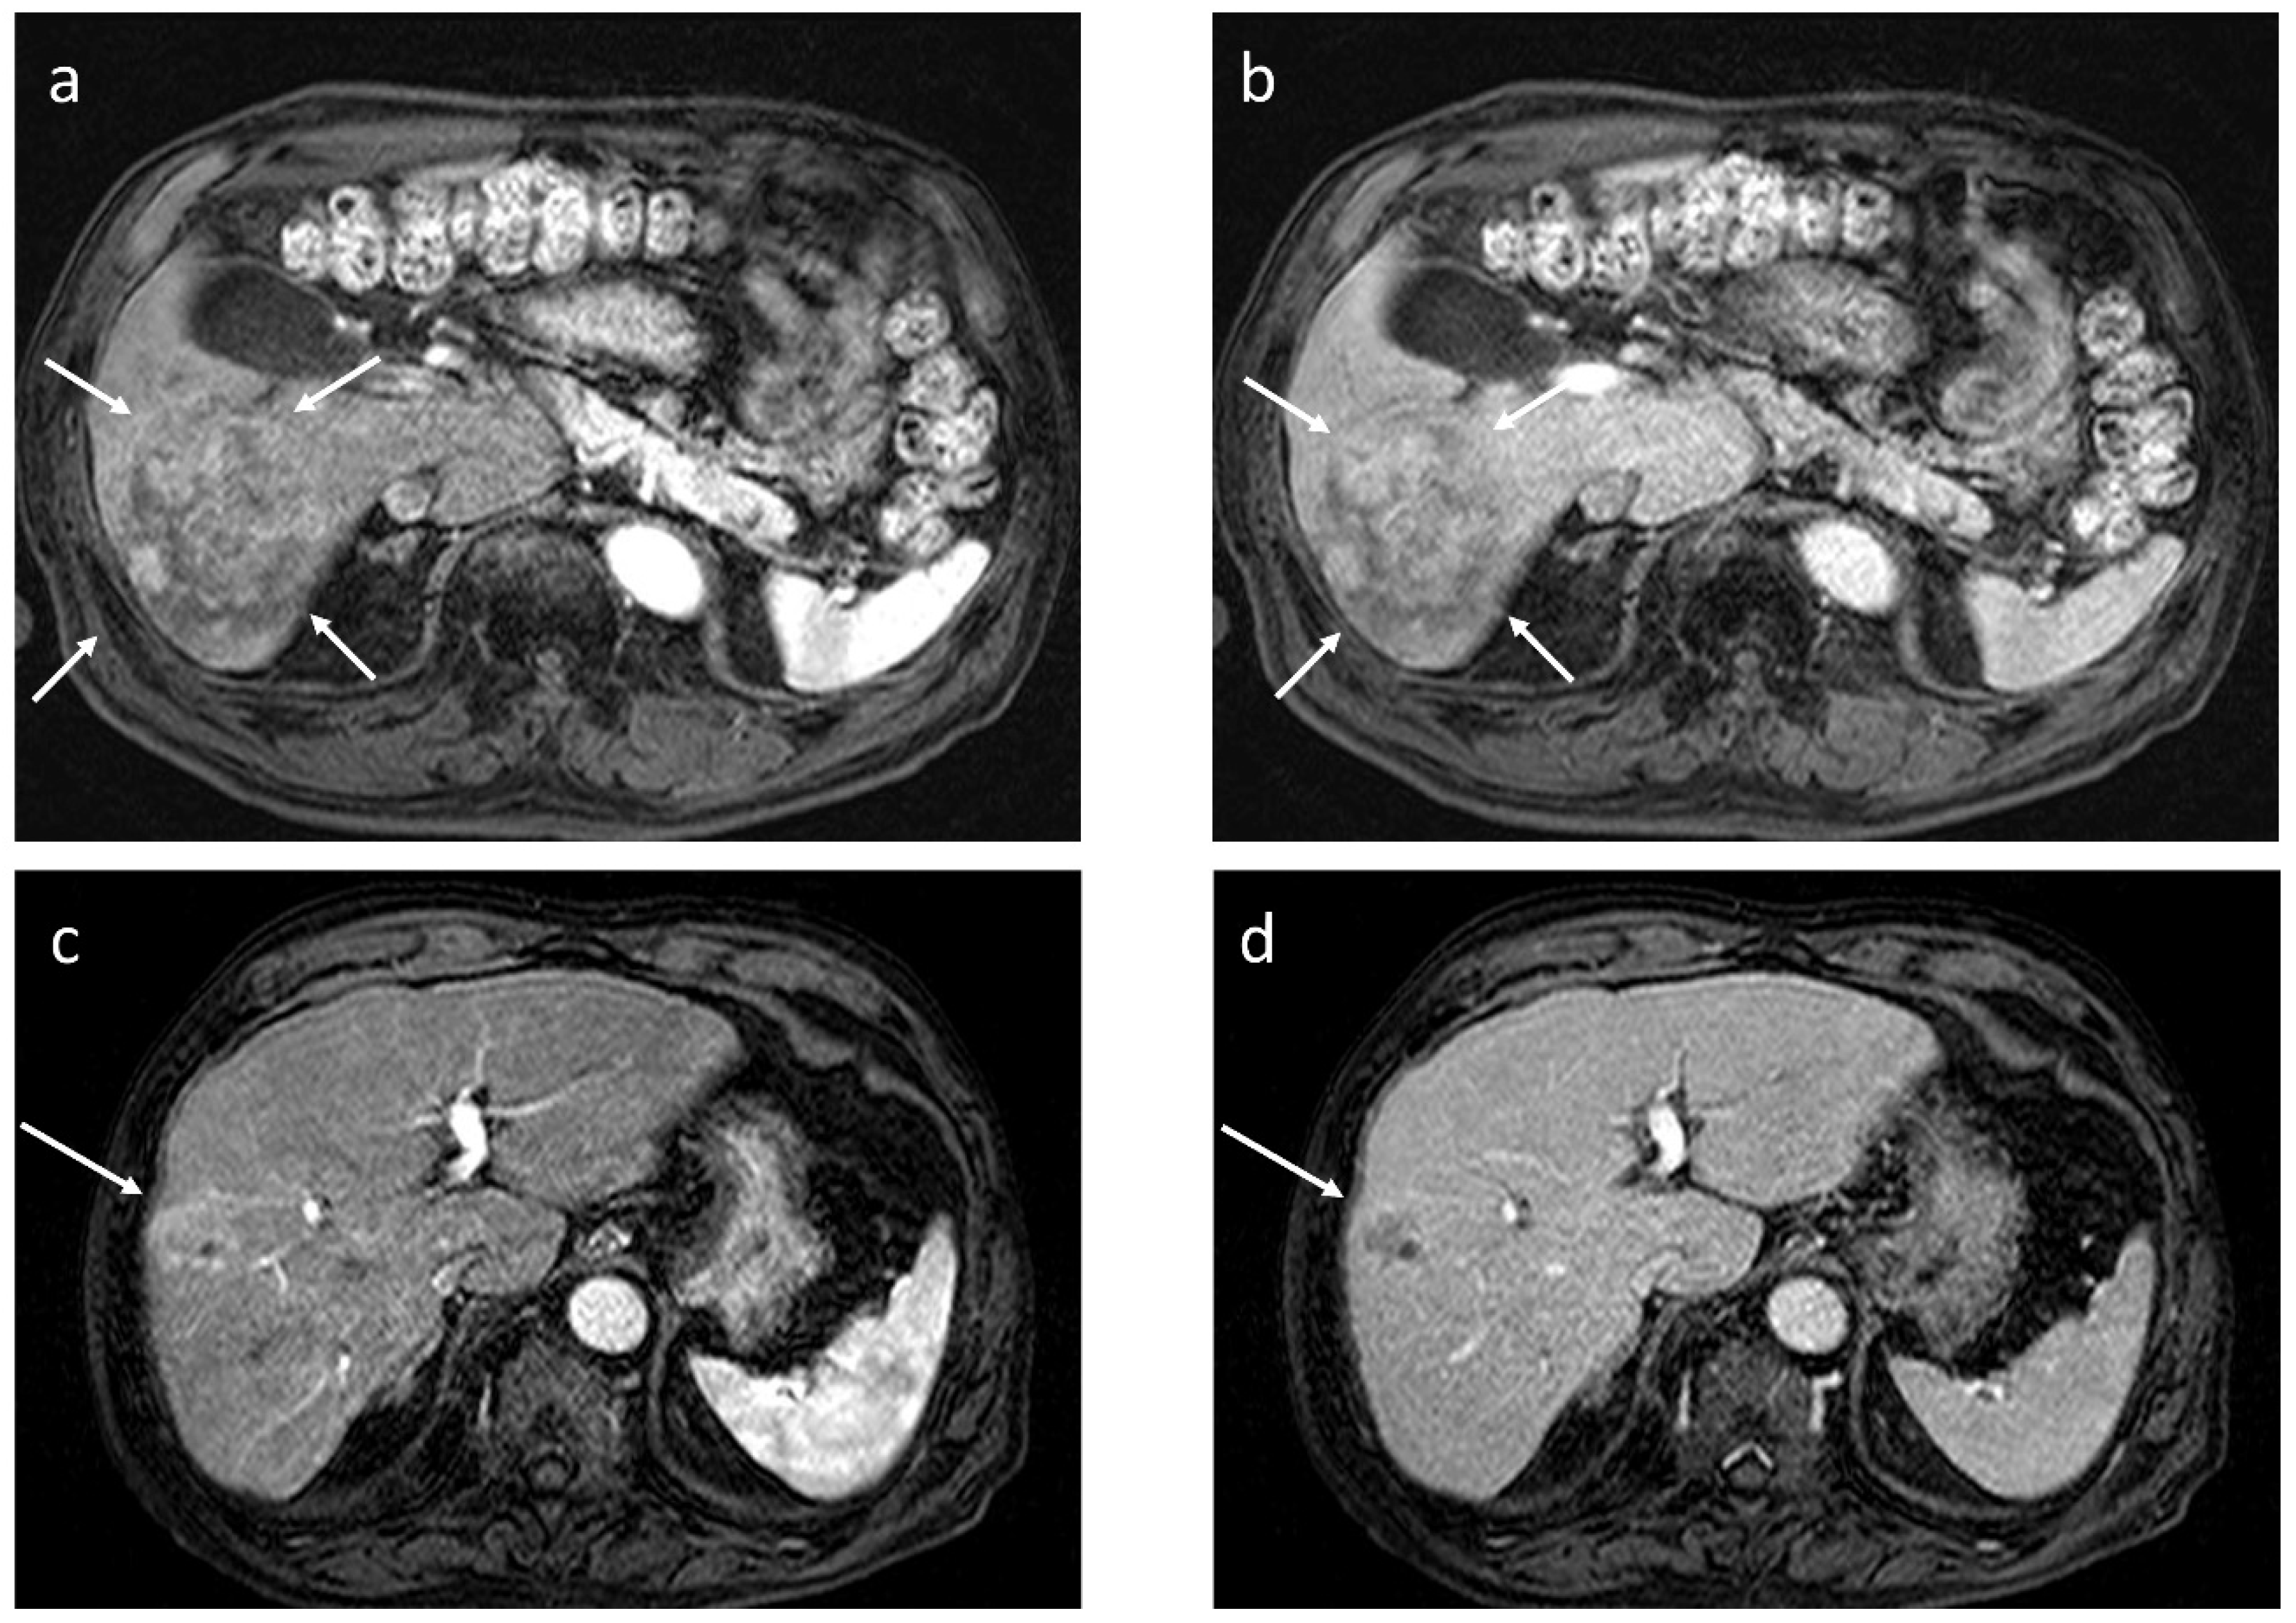

2.1. Washout at the PVP of CT or ECCM-MRI

2.2. Washout at the PVP of Gadoxetate-Enhanced MRI (EOB-MRI)

2.3. Washout at the Equilibrium Phase of CT